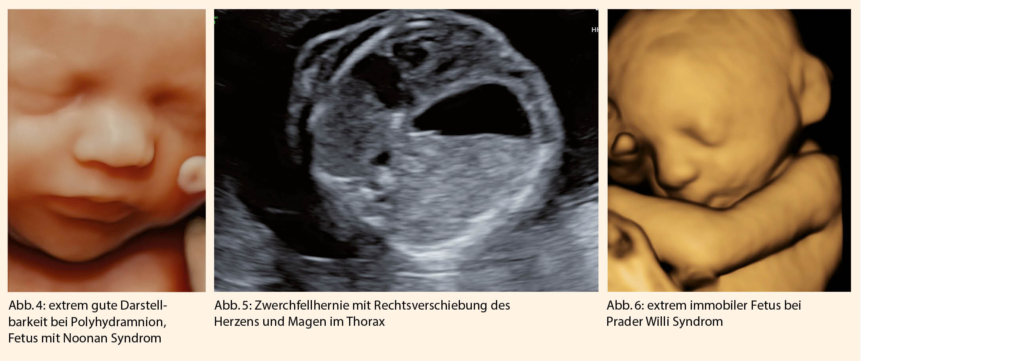

Vorteilhaft und hilfreich für die detaillierte Ultraschalldiagnostik ist die häufig sehr gute Darstellbarkeit bei gutem Ultraschallfenster (Abb. 4).